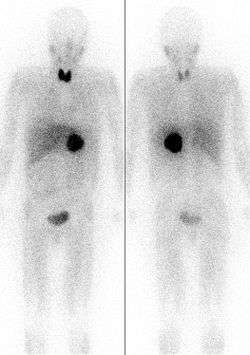

Of the many isotopes of iodine, only two are typically used in a medical setting: iodine-123 and iodine-131. Since 131I has both a beta and gamma decay mode, it can be used for radiotherapy or for imaging. 123I, which has no beta activity, is more suited for routine nuclear medicine imaging of the thyroid and other medical processes and less damaging internally to the patient. There are some situations in which iodine-124 and iodine-125 are also used in medicine.[8]

Due to preferential uptake of iodine by the thyroid, radioiodine is extensively used in imaging of and, in the case of 131I, destroying dysfunctional thyroid tissues. Other types of tissue selectively take up certain iodine-131-containing tissue-targeting and killing radiopharmaceutical agents (such as MIBG). Iodine-125 is the only other iodine radioisotope used in radiation therapy, but only as an implanted capsule in brachytherapy, where the isotope never has a chance to be released for chemical interaction with the body's tissues.

I) is a beta-emitting isotope with a half-life of 8.0249 days, and comparatively energetic (0.61 MeV) beta radiation, which penetrates 0.6 to 2.0 mm from the site of uptake. This beta radiation can be used for the destruction of thyroid nodules or hyperfunctioning thyroid tissue and for elimination of remaining thyroid tissue after surgery for the treatment of Graves' disease. The purpose of this therapy, which was first explored by Dr. Saul Hertz in 1941,[14] is to destroy thyroid tissue that could not be removed surgically. In this procedure, 131I is administered either intravenously or orally following a diagnostic scan. This procedure may also be used, with higher doses of radio-iodine, to treat patients with thyroid cancer.

The 131I is taken up into thyroid tissue and concentrated there. The beta particles emitted by the radioisotope destroys the associated thyroid tissue with little damage to surrounding tissues (more than 2.0 mm from the tissues absorbing the iodine). Due to similar destruction, 131I is the iodine radioisotope used in other water-soluble iodine-labeled radiopharmaceuticals (such as MIBG) used therapeutically to destroy tissues.